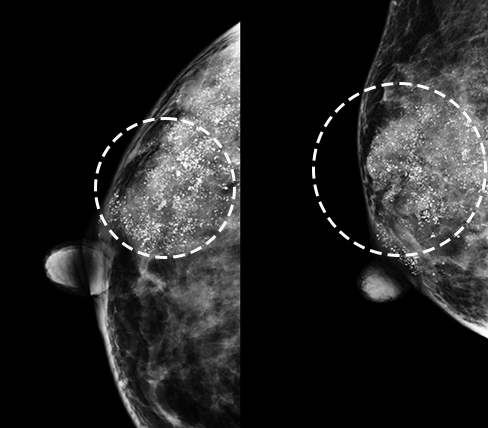

양성석회화 -

미세석회화 -

군집성 미세석회화

* 미세석회화: 0.5mm 이하로 작고 단위면적당 입자수가 많으며 크기와 모양이 균일하지 않음

* 군집성 미세석회화: 단위면적당 5~10개 이상 모여 있는 경우